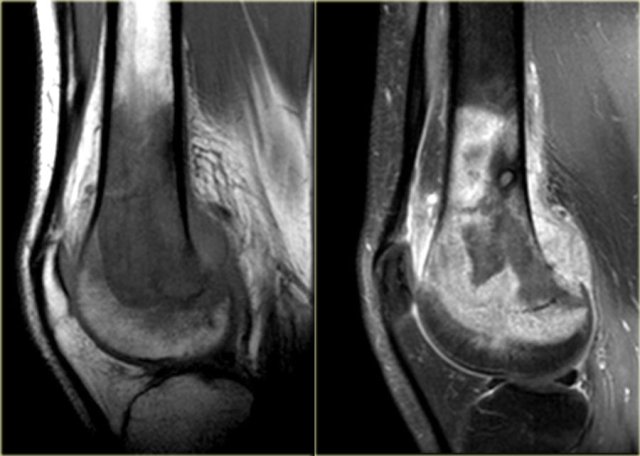

Here images of an osteosarcoma in the right femur.

It is barely visible within the bone, but an agressive periostitis is seen (arrow).

Continue with the MR-images.

The sagittal T1WI and Gd-enhanced T1W-image with fatsat show a large tumor mass infiltrating a large portion of the distal femur and extending through the cortex into the soft tissues.